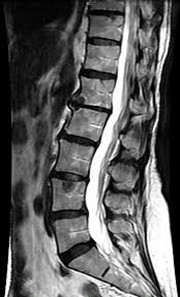

• conditions involving musculoskeletal system including the knee, shoulder, ankle, wrist and elbow as well as ligament, meniscus and rotator cuff tears

• injuries, tumors, and degenerative disorders of bone joints, spine, ligaments, meniscus in the skeletal muscular structure of the body